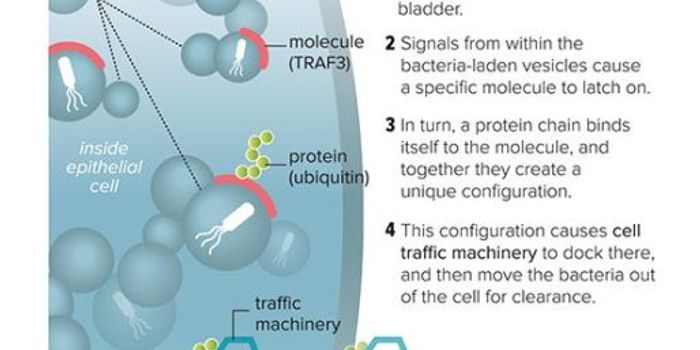

JUL 07, 2020MicrobiologyUrinary tract infections can be very painful and can cause nausea, chills, and fever. A pathogenic strain of E. coli is ...